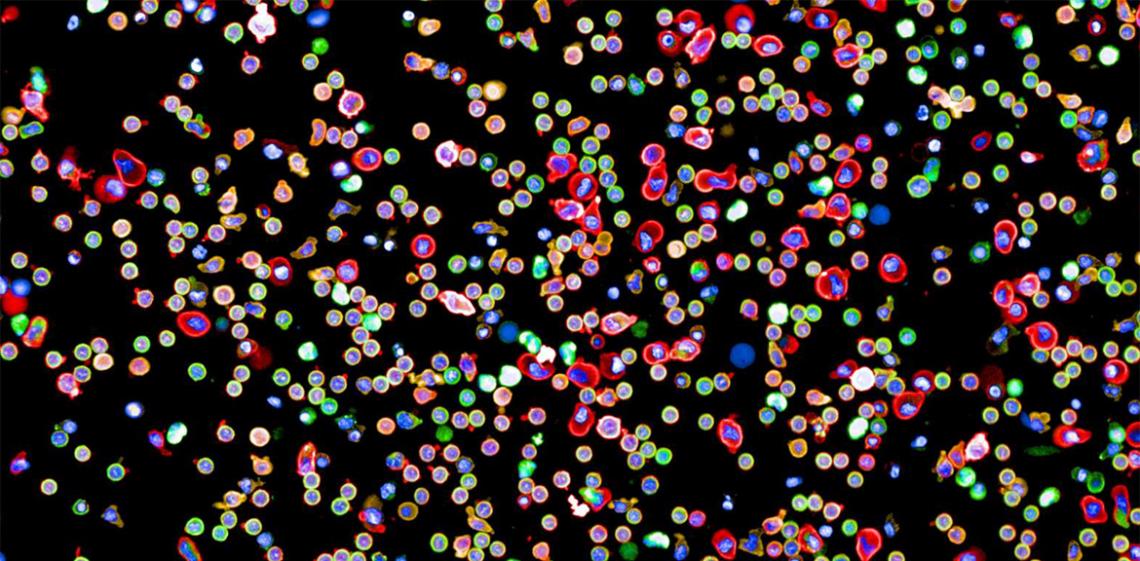

Image: Yannik Severin, Julien Mena, Berend Snijder / ETH Zürich

Researchers at ETH Zurich have created the first map of connection within the human immune system. The map shows how immune cells across the body link up and communicate to deal with threats.